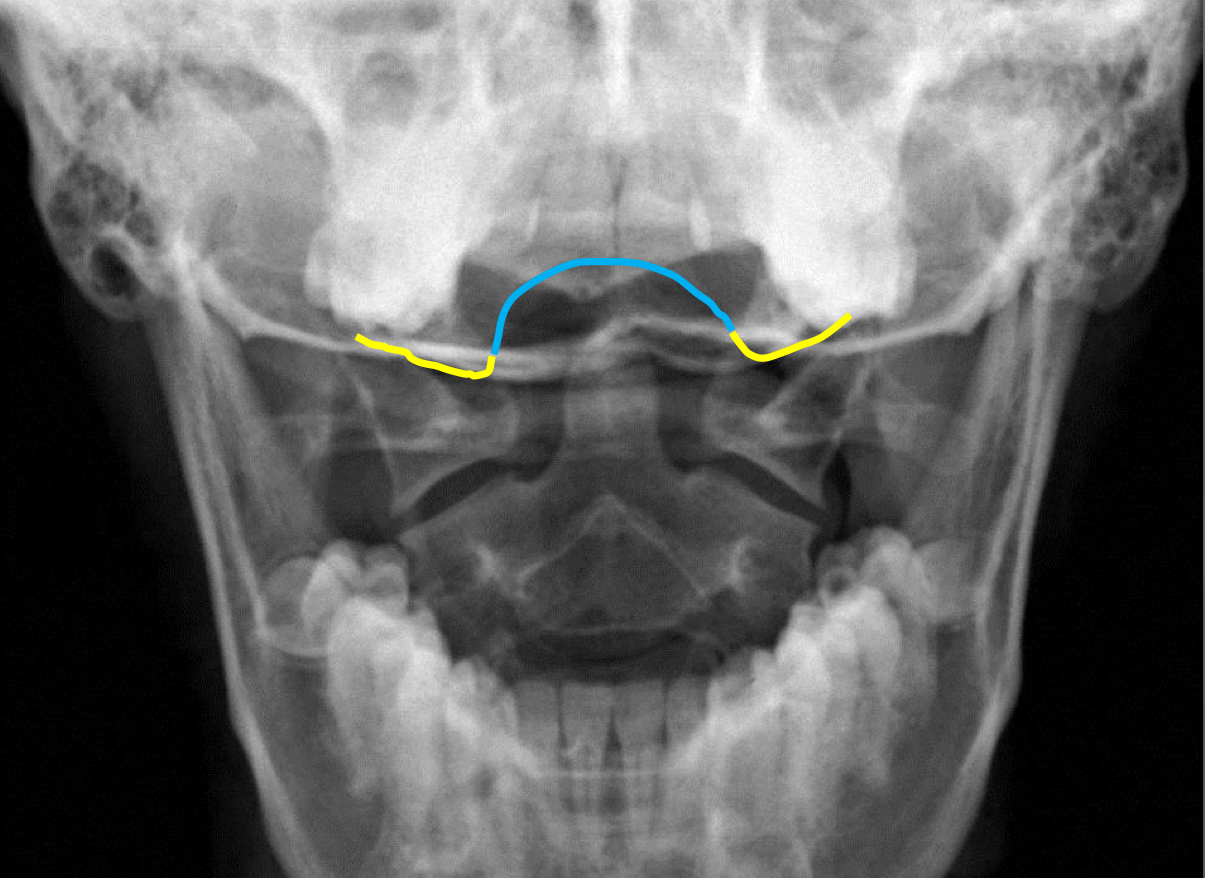

What view is this?

APOM

What is this - Yellow?

Occipital Condyles

What is this - blue?

Foramen Magnum

What is this?

C1 TVP/Lateral Mass Junction

What is this?

Odontoid Process

What is this?

C2 Spinous Process

What is this?

C2 Pedicle Shadows